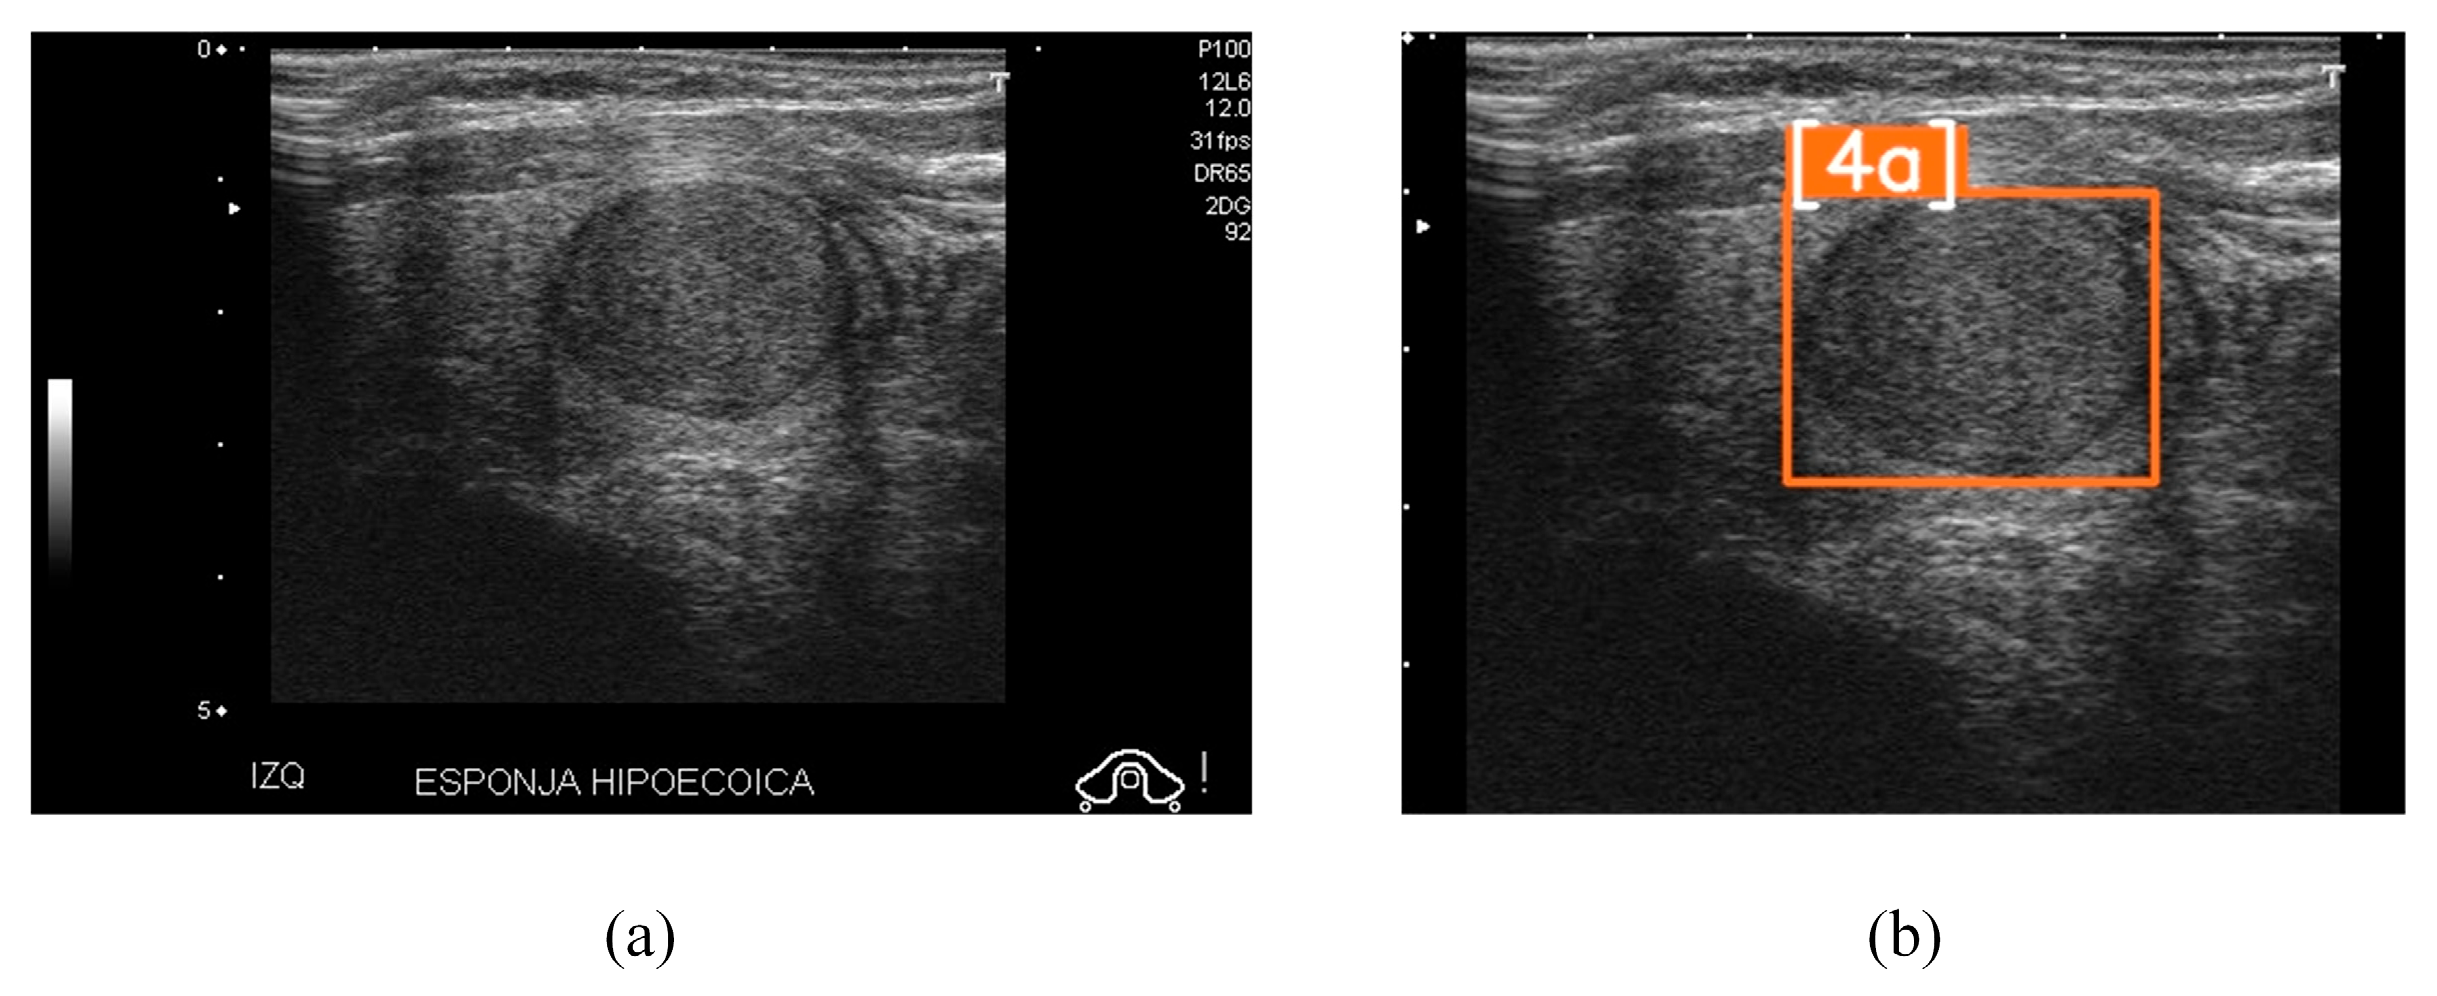

- [2] Benign (0% risk of malignancy);

- [3] No suspicious US feature (<5% malignancy);

- [4a] One suspicious US feature (5–10% malignancy);

- [4b] Two suspicious US features (10–80% malignancy);

- [4c] Three or four suspicious US features (10–80% malignancy);

- [5] Five suspicious features (>80% malignancy).